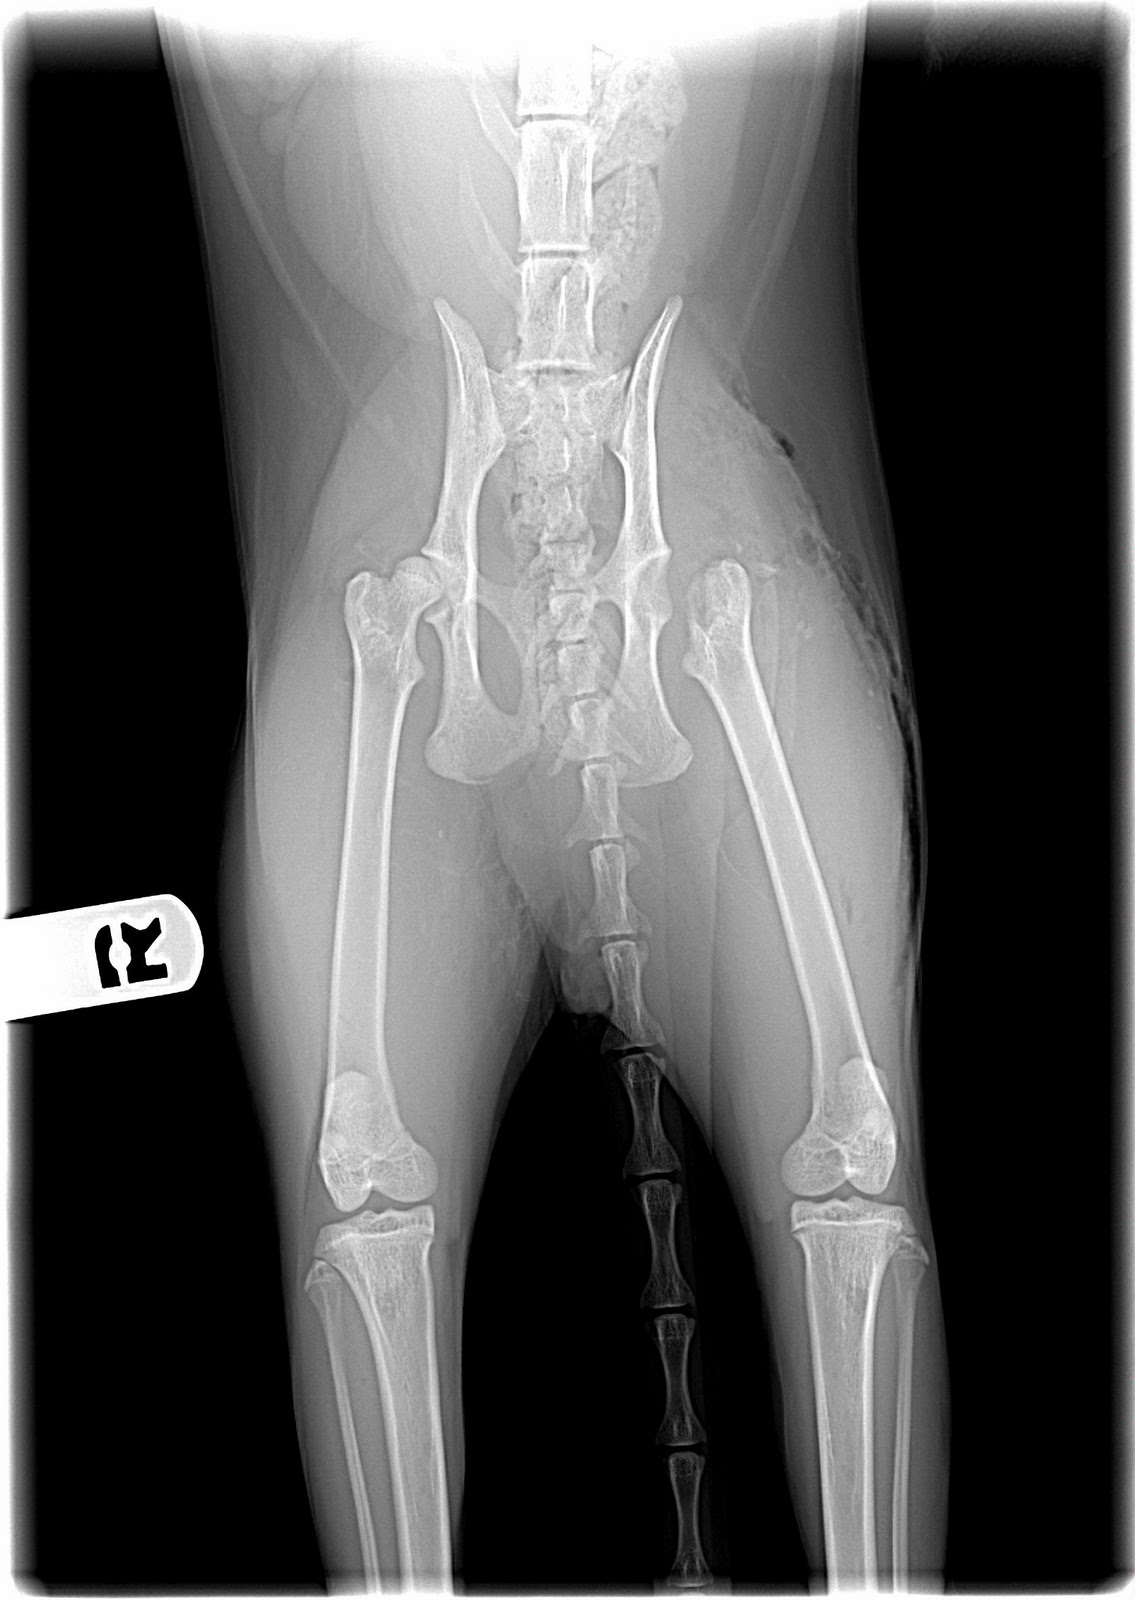

From www.vetlexicon.com

Radiography pelvis in Cats (Felis) Vetlexicon How Much Does It Cost To Fix A Cat's Broken Hip cost of surgical fracture repair in cats surgical fracture repair is costly, which is a reflection of the many processes required. the aim of treating a broken leg is to help the body heal the fracture as quickly as possible, and to return your cat to being able to use. according to a recent survey, the average. How Much Does It Cost To Fix A Cat's Broken Hip.